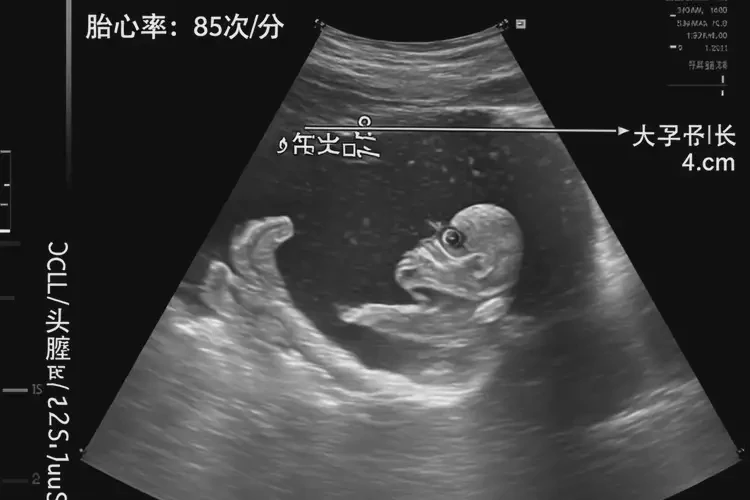

孕8周6天胎心80多還能保住嗎

胎心80多在孕8周6天的情況下,胎兒的存活情況并不樂(lè)觀。 正常情況下,孕8周的胎心率應(yīng)該在140-170次/分鐘之間。胎心率低于120次/分鐘被認(rèn)為是異常的,而80多次/分鐘的胎心率明顯低于正常范圍,可能表明胎兒存在嚴(yán)重的健康問(wèn)題。

孕8周6天胎心80多還能保住嗎(圖1)

二、胎心率80多的嚴(yán)重性

胎心率80多在孕8周6天的情況下,屬于明顯的異常。這種低胎心率可能表明胎兒存在嚴(yán)重的健康問(wèn)題,需要立即就醫(yī)進(jìn)行進(jìn)一步的評(píng)估和治療。